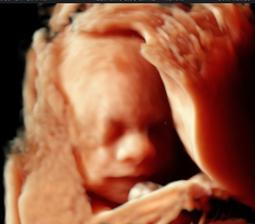

29.1. z vysledkov krvi sme zistili, ze cakame chlapceka, Viliama 😵 o par dni NT screening a zas ten pocit, ze co ak nebude vsetko v poriadku? tehotna sa stale necitim 🙂

NT screening dopadol fantasticky, cakame nadherne zdrave dietatko, dakujem! 😵